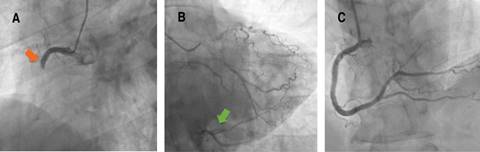

A 57-year-old man with obesity, hypertension and former smoker as cardiovascular risk factors, and previous history of Sjögren’s syndrome and gastroesophageal reflux, consulted his general practitioner for chest pain compatible with angina on moderate exertion. The ECG showed a right bundle branch block (RBBB) not present in previous ECGs (Figures 1 and 2). Treatment with ASA 100 mg od, statin and beta-blocker were started, and the patient was referred preferentially to cardiology for further evaluation. A conventional stress test was performed two weeks later. However it was stopped in the middle of the second stage of the Bruce protocol (6.8 METs and 88% of maximum heart rate) due to angina, without presenting electrocardiographic repolarization changes suggestive of ischemia. Progressive angina persisted despite treatment, so the patient consulted the emergency room four days later due to persistent chest pain at rest. The ECG did not show changes compared to the previous one, however biomarkers of myocardial necrosis were elevated (peak Tn I-hs 5140 pg/mL and CK 411 U/L), so the patient was admitted to the coronary care unit with the diagnosis of non-ST-segment elevation myocardial infarction (NSTEMI). On admission, an echocardiogram showed akinesia of the inferior basal and inferolateral basal segments with preserved parietal thickness, and normal biventricular ejection fraction, without significant valve disease or other notable findings. Antithrombotic therapy was started with ASA 100 mg, clopidogrel 300 mg, fondaparinux 2.5 mg sc, and intravenous nitroglycerin, with slight improvement, but without complete resolution of angina, so an emergent coronary angiography was decided to perform. Acute thrombotic occlusion of the right coronary artery (RCA) was observed, with collateral circulation (CC) from the left coronary tree, which did not present significant stenosis (Figure 3). Angioplasty was performed with implantation of a drug-eluting stent, with subsequent resolution of angina and disappearance of the RBBB. The patient presented a favorable clinical evolution, being discharged on the fourth day of admission.

When a patient presents with symptoms suggestive of angina, a 12-lead resting ECG should be performed immediately to assess repolarization changes suggestive of ischemia, especially to identify early persistent ST-segment elevation, which requires emergent reperfusion.1 Characteristic ECG abnormalities in ACS without persistent ST-segment elevation include ST-segment depression, transient ST-segment elevation, and T-wave changes. Even though the ECG in this setting may be normal in more than 30% of patients,2 If the patient has signs or symptoms suggestive of ongoing myocardial ischemia and the standard leads are inconclusive, additional leads should be recorded. The left circumflex artery occlusion may be detected only in posterior leads (V7-V9) or right ventricular MI only in V3R and V4R.3 In case of persistent or recurrent symptoms or diagnostic uncertainty, it is also recommended to obtain additional 12-lead ECGs. In patients with a preexisting left bundle branch block (LBBB), specific ECG criteria (Sgarbossa’s criteria) help detect candidates for immediate coronary angiography.4 Patients with high clinical suspicion of ongoing myocardial ischemia and LBBB, regardless of whether it was previously known, should be treated similar to those with STEMI.1 In patients with RBBB, ST-elevation indicated of STEMI, while ST-segment depression in the leads I, aVL, and V5-6 is indicative of NSTE-ACS.5 Our patient did not strictly meet ECG criteria for persistent ST-segment elevation. However the patient persisted with symptoms of ongoing angina despite treatment and presented with a recent RBBB, so it was decided to perform emergent coronary angiography. Given the good heterocoronary CC observed in the infarcted territory, the infarct size was smaller than expected, as well as the poor electrocardiographic expressiveness. Therefore, it is important to always keep in mind the possibility of a MI with acute occlusion of a coronary artery in the presence of persistent angina despite adequate treatment and few repolarization abnormalities (even with a normal ECG) or new bundle branch block.